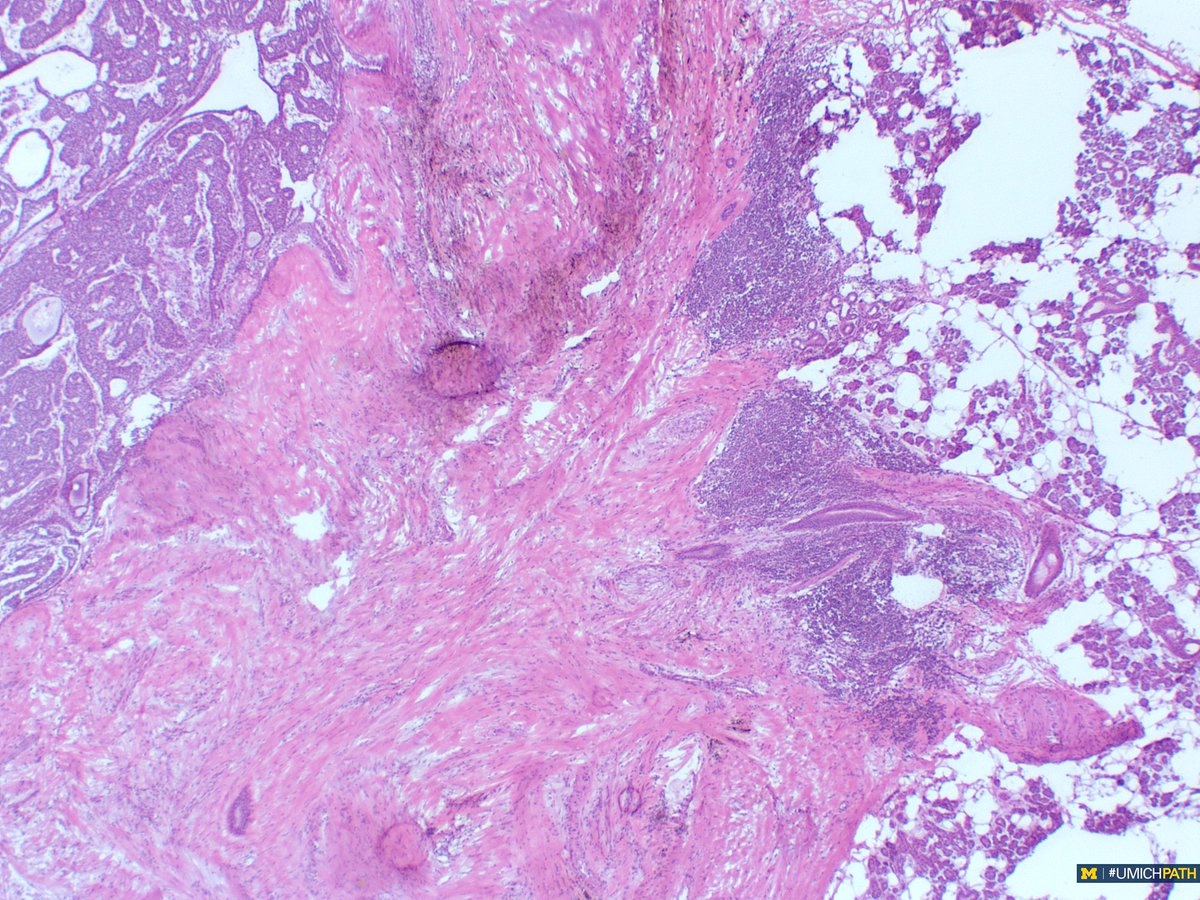

@UMichPath

Michigan Pathology

2 years

🔬: #COTW from @MeredithKHerman! Intraoperative Frozen Consult of a parotid mass from a 60yo F. What is your differential diagnosis? #UMichPath #Pathology